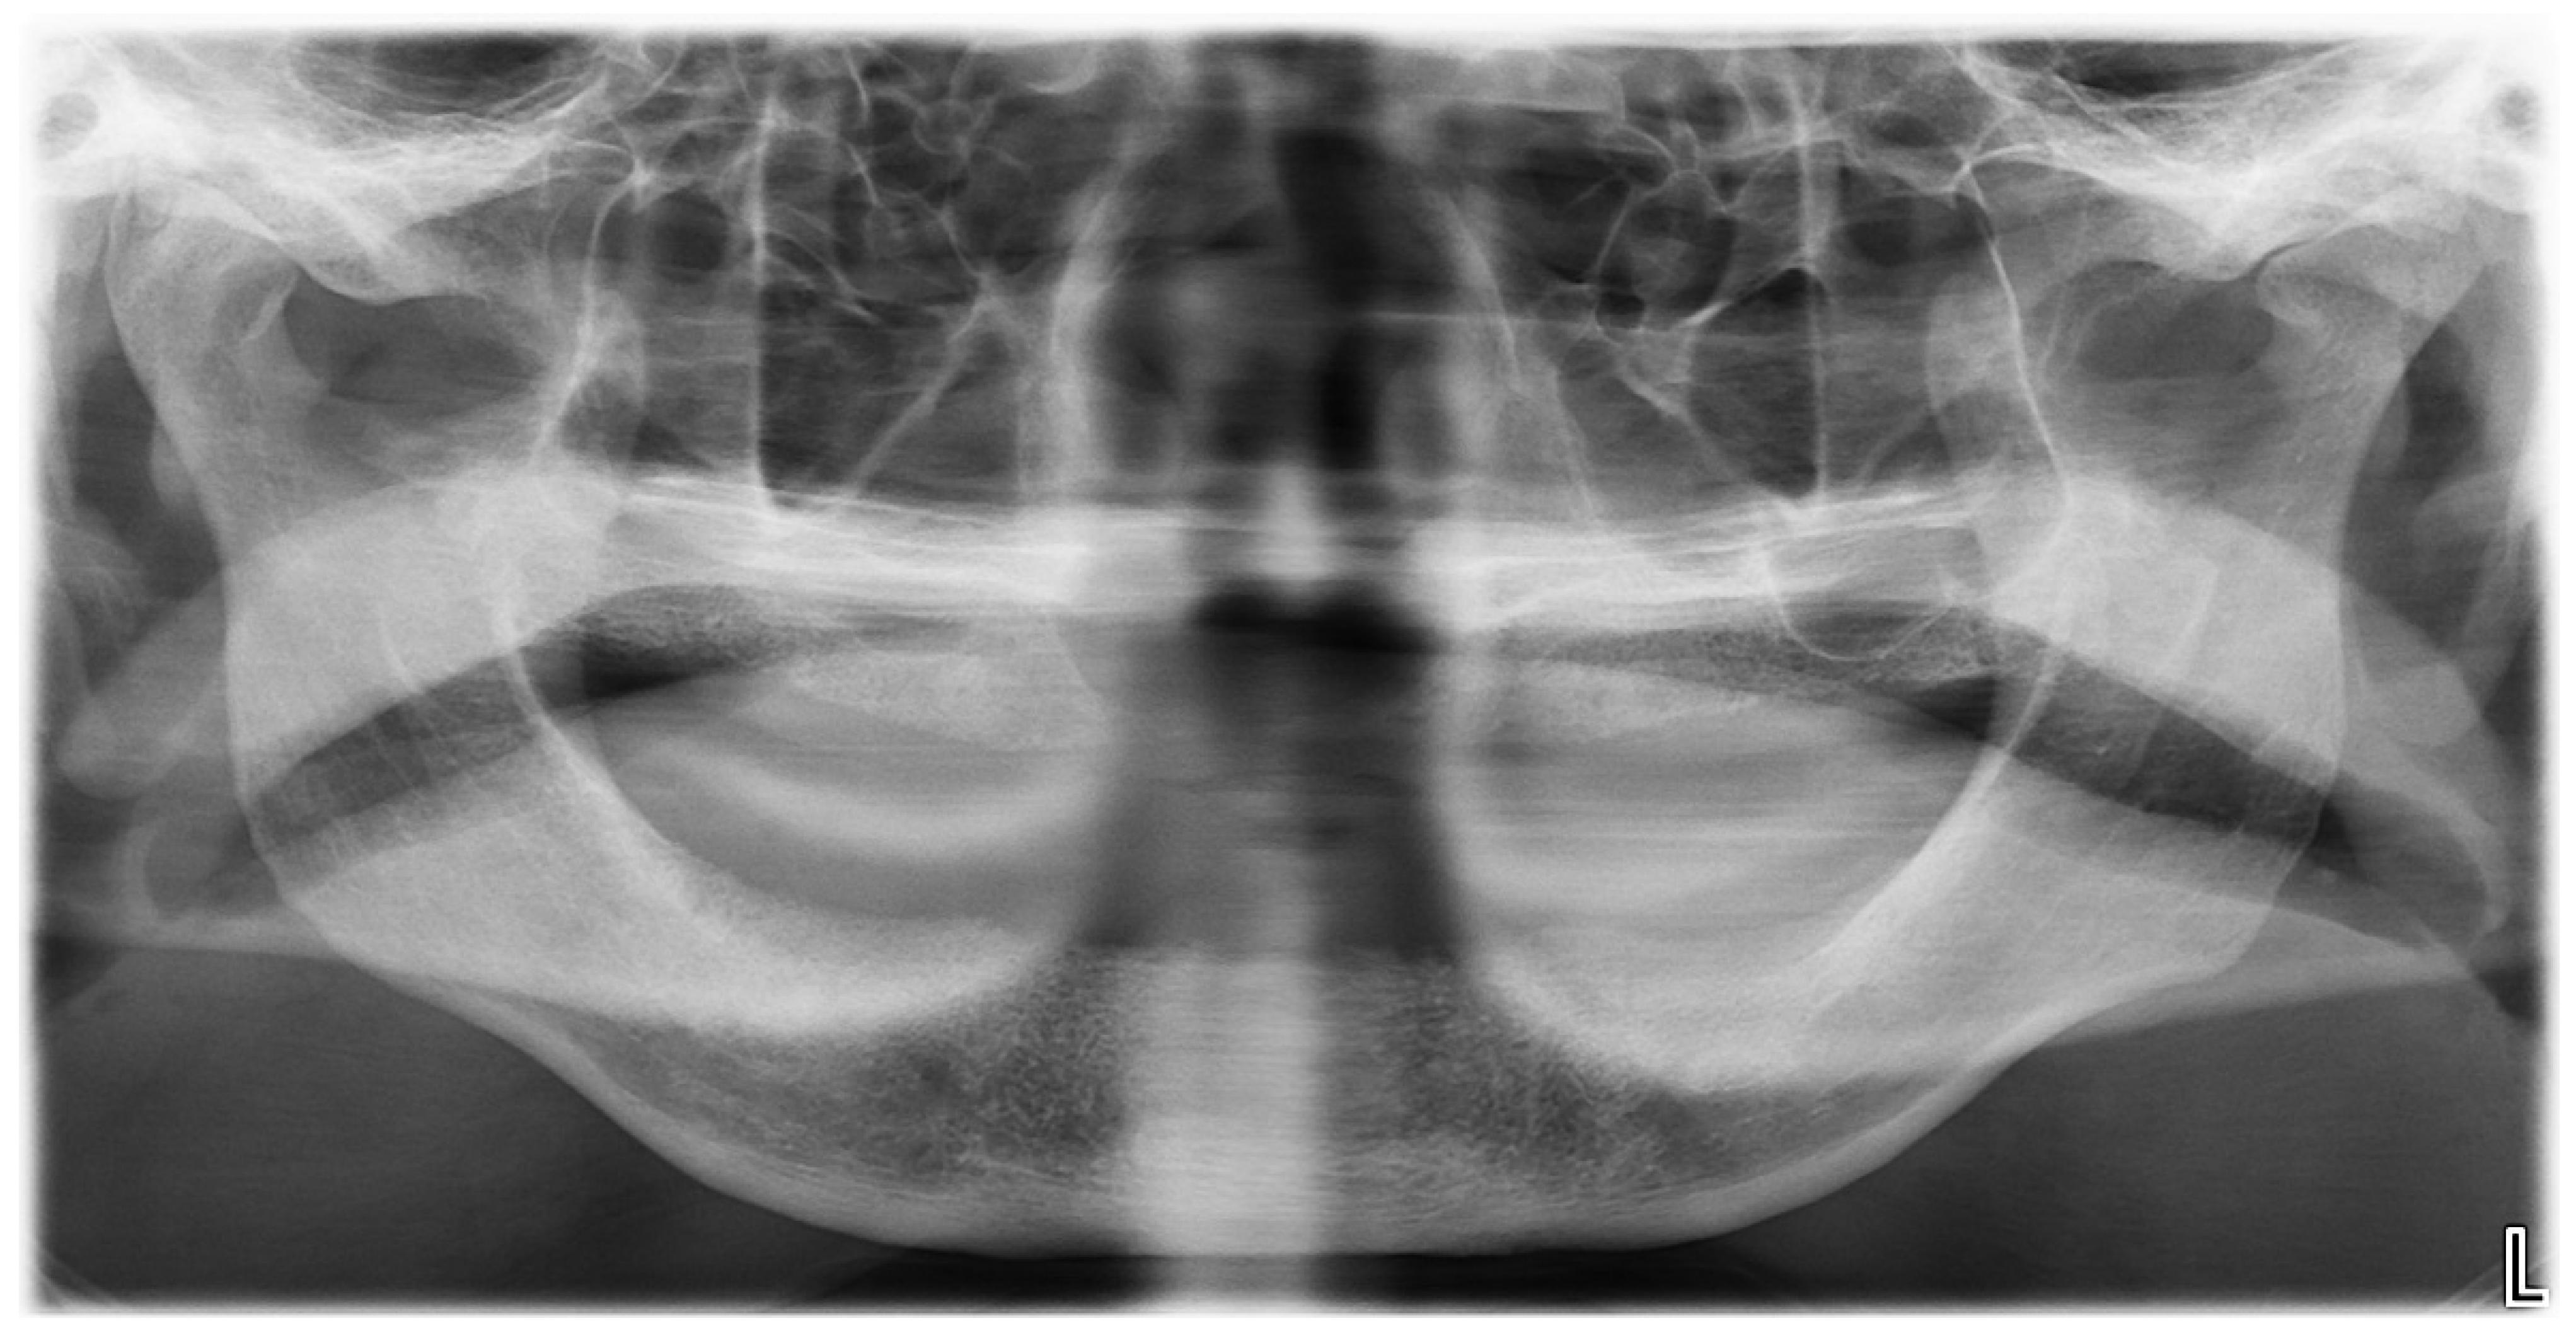

An OPG X-ray revealed a radiotransparent lesion located in the area of the incisors and canines (Figure 1).

Figure 1.

Panoramic X-ray at first examination.